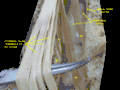

- Spinal cord. Spinal membranes and nerve roots.Deep dissection. Posterior view.

Spinal cord. Spinal membranes and nerve roots.Deep dissection. Posterior view.